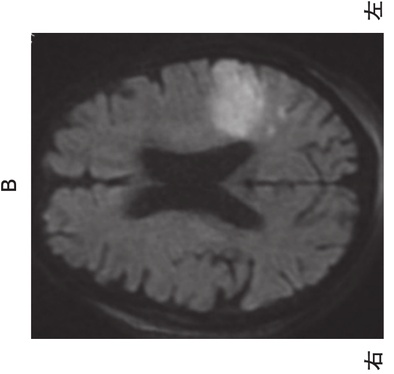

80歳の男性。糖尿病で治療中。意識混濁と呂律緩慢のため救急車で搬入された。初診時の心電図 と頭部MRI拡散強調像 を別に示す。この疾患の再発予防に使用される最も適した薬剤はどれか。

t8K6Utr3i_

o6UiKcVHsQ

1

硝酸薬

2

β遮断薬

3

抗凝固薬

4

ステロイド薬

5

抗てんかん薬